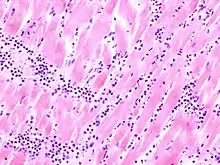

Acute myocardial infarction

Der Myokardinfarkt muss mind. 6 - 12 Stunden überlebt werden, bevor er morphologisch sichtbar wird!

Mikro: Koagulationsnekrose, Einblutungen. Die Myozyten zeigen eine verstärkte Eosinophilie und Kontraktionsbanden quer durch die Herzmuskelfasern. Typische Zellparameter wie Querstreifung, Zellkerne und Zellgrenzen gehen verloren. Das Infarktareal wird von einer Hyperämischen/hämorrhagischen Randzone begrenzt. Im Verlauf zunehmende leukozytäre Demarkation und Phagozytose des nekrotischen Gewebes, sowie Einwanderung von Fibroblasten mit Ausbildung eines narbigen Ersatzgewebes.

![]() Myokardinfarkt 7. Tag (Abräumphase), Sektionspräparat, H&E. |